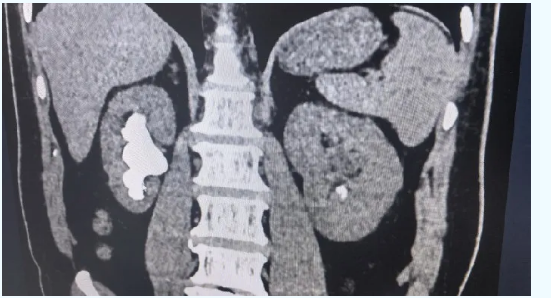

59岁的胡先生(化名)近一年来血压总是居高不下,最高一次达到230/100mmHg,还伴有胸闷、胸痛。他一度以为自己是心脑血管出了问题,住进洛阳白马医院内科后,医生详细检查发现——双侧肾脏都长满了结石,其中右肾有一颗直径约7厘米的鹿角形巨大结石,几乎占满了整个肾盂。

正是这颗大石头长期压迫肾脏、影响肾脏供血,导致身体不断分泌升高血压的物质,引发了顽固性肾血管性高血压。这种情况,光吃降压药效果往往不理想,只有把结石取出来,血压才有希望真正回落。